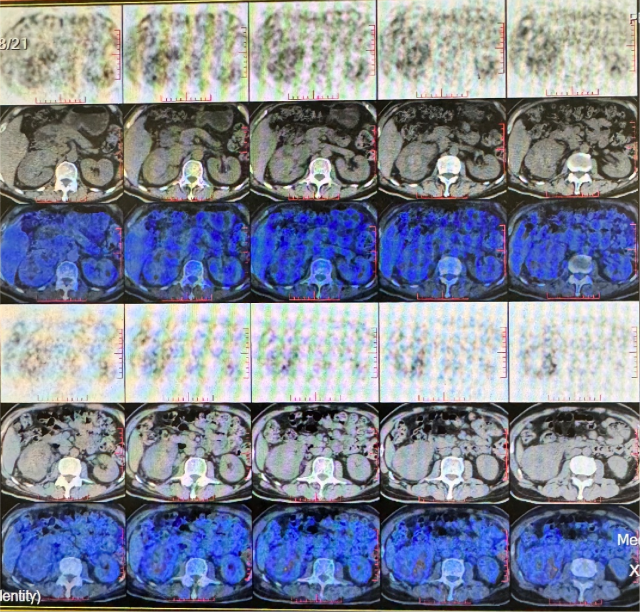

PETCT(2022.10):1. 左侧肾上腺结节灶,糖代谢增高,转移瘤可能性大;2. 左肾多发结节状突起,糖代谢增高,考虑转移瘤,需结合增强 CT 综合判断;3. 右下肺切除术后,术区未见复发;4. 右侧胸壁局部增厚、糖代谢增高,术后改变?建议追踪。

靶免联合治疗 1 年后复查

CT(2023.7.17):1. 左肾上腺结节、左肾结节及肿块较前明显增大:转移?左肾 CA 并左肾内、肾上腺转移?2. 腹膜后淋巴结较前增大,转移可能;3. 余况基本同前。

2023.7 开始予以伏罗尼布单靶治疗

CT(2023.12.6):1. 左肾上腺结节较前稍缩小、左肾结节及肿块较前稍缩小;2. 腹膜后淋巴结转移灶同前;3. 余况基本同前。

肝、肾功能变化情况

伏罗尼布治疗 2 年后病变进展

CT(2025.4.7):1. 左肾上腺肿块较前明显增大;2. 左肾结节及肿块部分较前增大;3. 腹膜后淋巴结同前;4. 右侧胸膜结节状增厚较前增大,建议追踪;5. 余双肺情况基本同前。